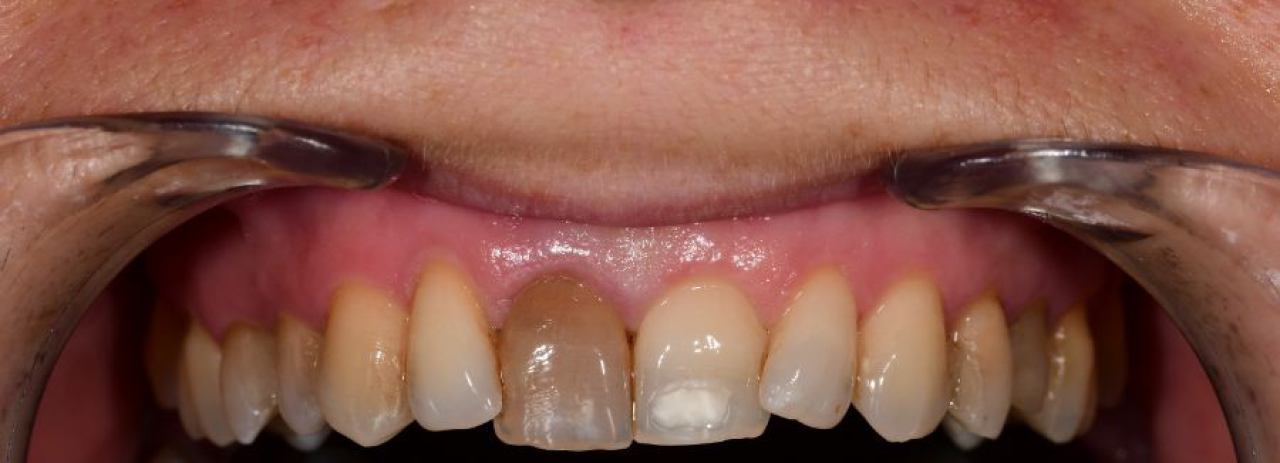

Estetska dentalna medicina

Izbjeljivanje zubi i zubne ljuskice zaštitni su znak Hollywoodskog osmijeha. Izbjeljivanje nije štetno za zube i ne oštećuje caklinu.

Ukoliko niste zadovoljni svojim osmijehom tu je DSD ili Digital Smile Design kojim u okvirima naših mogućnosti ispunjavamo vaše želje „Hollywood smile" ljuskicama, minimalno invanzivnim preparacijama zuba.

Marković Dental Clinic uvijek na prvom mjestu ima zdravlje zubi i zadovoljstvo svakog pacijenta. Koristimo najmoderniji software gdje je pacijentu moguće virtualno prikazati nove zube te kasnije kreirati novi osmijeh protetskim radom, ljuskicama, krunicama ili mostovima.